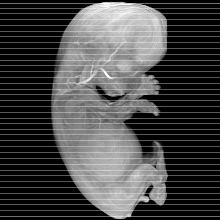

Carnegie Stage 23 (56 post-ovulatory days)

Most embryos at stage 23 are approximately 56-57 postovulatory days old and measure 23-32 mm in length. Distinguishing criteria for this stage include fusion of the eyelids at the medial and lateral margins, clear distinction of the subdivisions of the upper and lower limbs, the forearms appear at or above the level of the shoulders, the superficial vascular plexus of the head is very close to the vertex, and the external genitalia are well developed but not always sufficiently to distinguish the embryo's sex.

(NOTE: These specimens are late stage 23.)